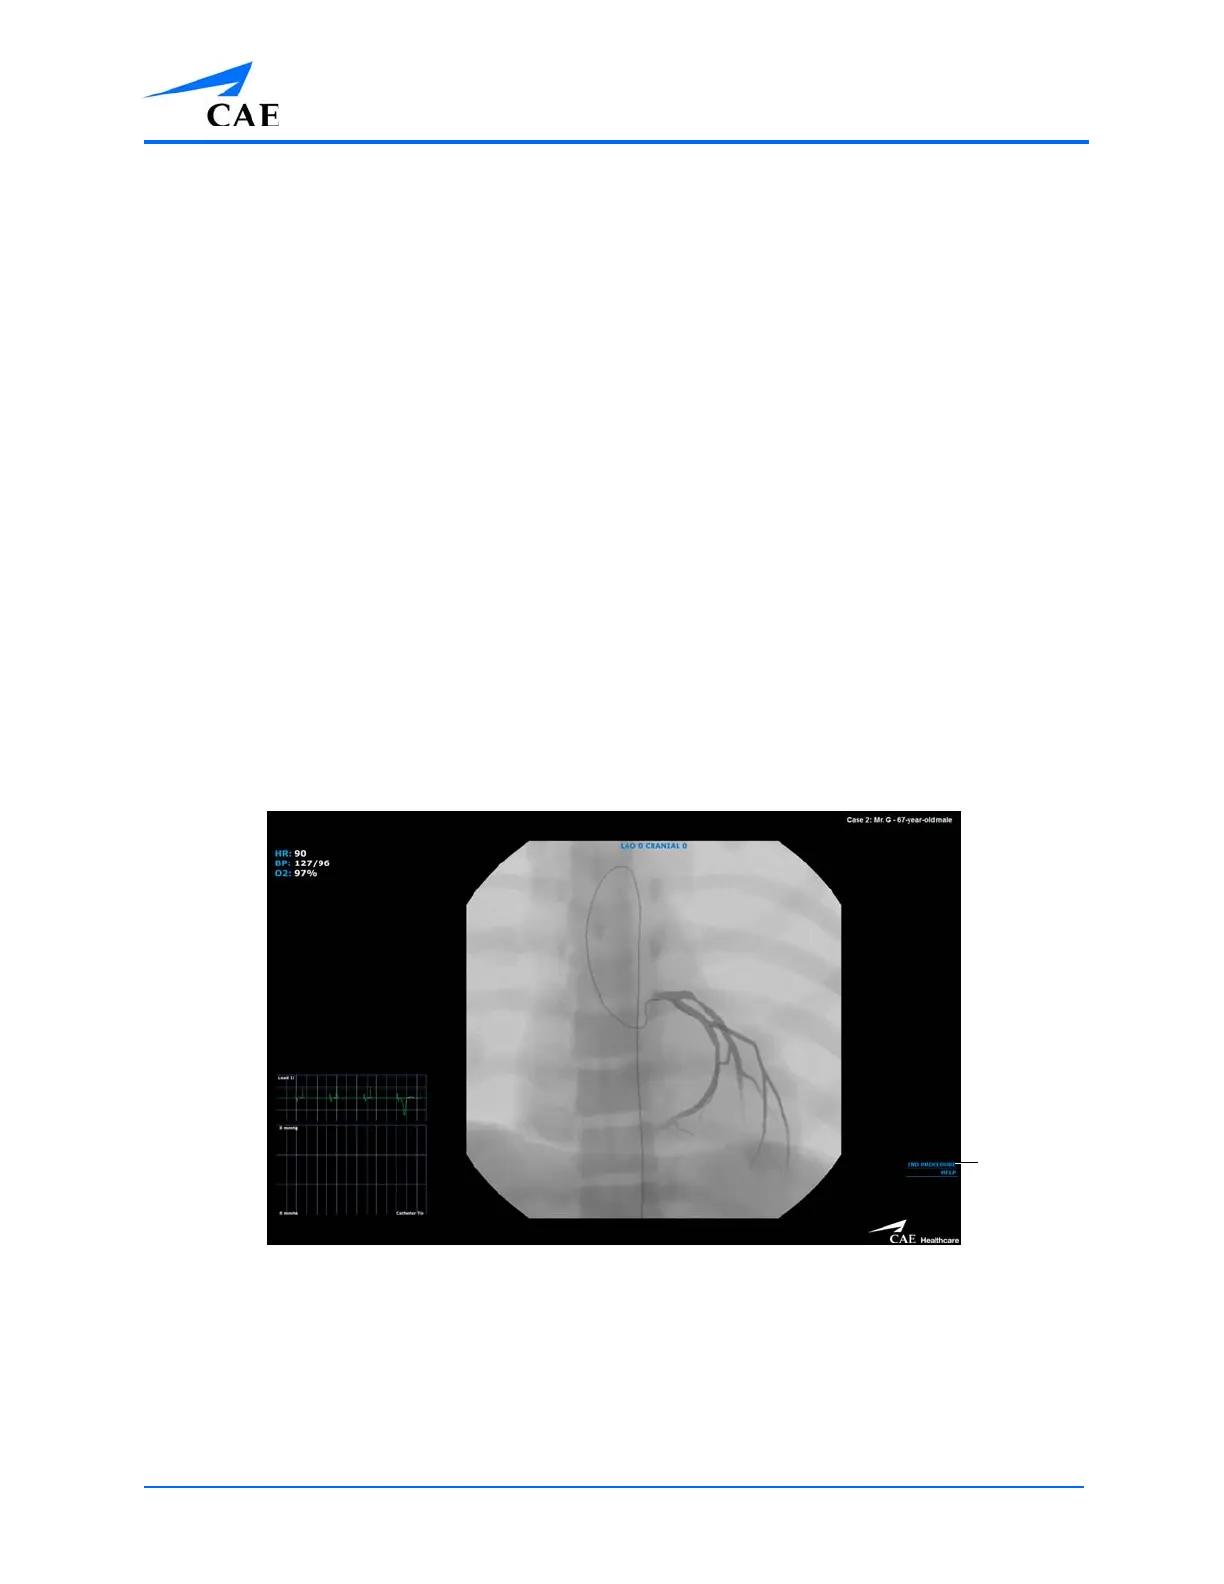

To end a simulation manually, from the simulation screen, click the End Simulation button.

The Simulation Screen

The End

Simulation

button

Table of Contents